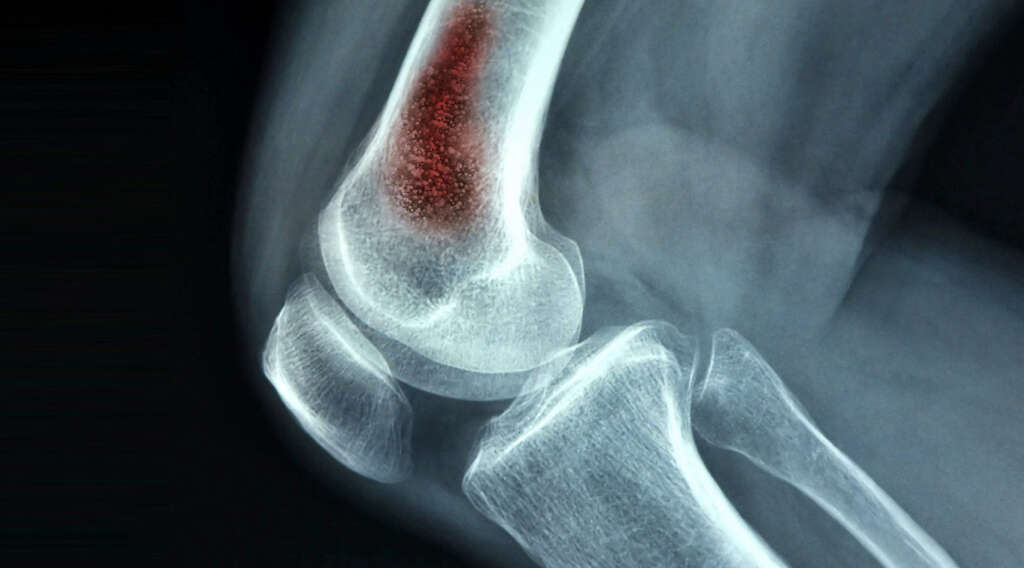

Osteomyelitis is an infection that occurs in the bone. Though rare, it can cause potentially serious complications. If it is severe enough and other treatment options have not been successful, you may require an amputation. However, thanks to research into the condition, other treatment options are usually effective, especially if the infection is caught early on.

One of the most serious complications is osteonecrosis, or bone death. This can occur when the infection impedes circulation within the bone, cutting off the blood supply to a certain area. Once osteonecrosis has set in, the only treatment option available is to remove the area of dead bone tissue.

Imaging exams such as MRI or X-ray can identify damage to the bone due to osteomyelitis. Sometimes your doctor performs a procedure to take a sample of tissue from the infected bone. The sample is then sent to a lab and tested for the presence of foreign organisms. This test is called a biopsy.